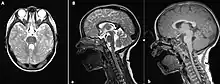

| (A) MRI Brain, axial T2 sequence showing enlarged superior cerebellar peduncles and vermian hypoplasia resulting in characteristic "molar tooth" appearance; (B) MRI Brain, sagittal T2 (a) and T1 (b) sequences showing vermian hypoplasia, predominantly at the superior aspect | |

The disorder is characterized by the absence or underdevelopment of the cerebellar vermis and a malformed brain stem (molar tooth sign), both of which can be visualized on a transverse view of the head MRI scan.[19] Together with this sign, the diagnosis is based on the physical symptoms and genetic testing for mutations. If the gene mutations have been identified in a family member, prenatal or carrier diagnosis can be pursued.[6]